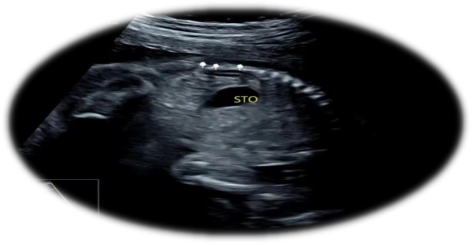

单侧肾缺如的超声表现:

1.一侧肾脏未探及

2.肾上腺平卧征

3.彩色多普勒超声显示缺如侧肾动脉亦缺如。

超声科医生在诊断单侧肾缺如时都非常谨慎,需要非常仔细地检查腹腔内尤其是盆腔内有无异位肾存在,才高度怀疑单侧肾缺如。